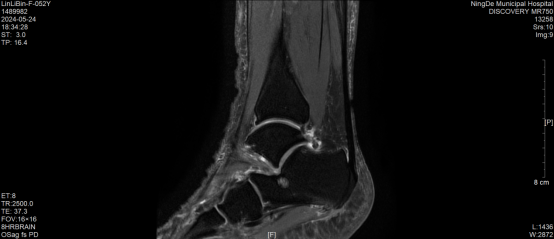

“我的右脚根部已经肿痛一个月了。”近日, 52岁的林女士到我院骨科就诊,恰逢上海市第一人民医院运动医学科陈疾忤名医“师带徒”工作室专家付国建到我院开展诊疗活动。付国建对患者进行踝关节MRI检查后判断患者的病因:经常踝关节扭伤,距腓前韧带损伤,存在踝关节不稳定,导致踝关节软骨损伤、韧带进一步损伤,继发骨质增生、骨赘形成,遂建议患者进行“踝关节镜下修复外侧副韧带手术”。

踝关节前后骨赘增生,出现撞击征。

距骨后内侧角处出现软骨损伤

距腓前韧带断裂

术后前后增生骨赘清除